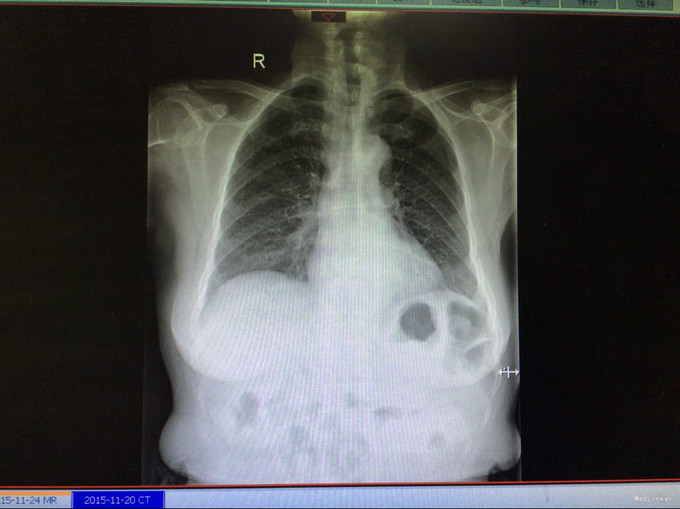

查体:生命体征平稳。神智清,查体合作,面容正常,淋巴结未触及肿大。双肺听诊呈清音,为闻及干湿罗音及哮鸣音;心率78次/分,律齐,无异常心音及心脏杂音;腹平软,肝脾肋下未及,未触及肿块,无压痛及反跳痛,肠鸣音正常。双下肢无水肿,生理反射存在,病理反射未引出。专科查体:无明显异常。辅助检查:湖北省中医院CT示:胰腺占位。CT检查示:1.结合原CT、MR检查,胰腺体尾部及周围异常改变,考虑胰腺炎伴坏死囊性变可能性大,与2015-11-20CT相比较,囊性病变略缩小;腹膜后淋巴结增多增大,大致同前;2. 所及肝脏多发囊肿;肝右叶后段其中一个病变边缘可疑强化,大小与前次相仿;3. 左侧肾上腺饱满。 MRI检查示: 胰腺体尾部及周围异常改变,考虑胰腺炎伴坏死囊性变可能性大,合并肿瘤性病变待排,病变累及腹膜伴腹膜后淋巴结增多增大,腹腔少许积液,请结合检查结果考虑;2. 所及肝脏多发囊肿;肝右叶后段其中一个病变边缘可疑强化,需鉴别于血管瘤与转移性病变,建议随访复查;3. 左侧肾上腺饱满;4. 所及右侧胸廓外小结节(层面16-7),直径约4mm,不除外右乳的病变:5. 所及腰椎骨性纵裂畸形。病理检查:(胰体尾部肿块穿刺组织)高分化腺癌,考虑为IPMN相关性浸润性癌。